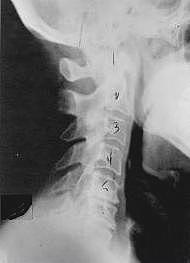

Phase One Subluxation Degeneration is seen in subluxations that have been present for up to twenty years. This phase is characterized with a loss or change in the normal curve in the spine. On this example you can see that the normal forward (lordotic) curve is lost. This spine even has developed a reverse curve in the neck. The disc spaces have also begun to exhibit a slight change in shape. One good point is that the bodies of each of the vertebrae (the square part in front) still exhibits clean clear borders. Segmental motion may be abnormal but overall motion is probably not affected. Chiropractic reconstructive care for a phase one can take from 6 to 18 months. More than 80% of people with Phase One Subluxation Degeneration have no pain. Therefore, if left uncorrected, phase one continues to progress with time until it eventually reaches the next phase.